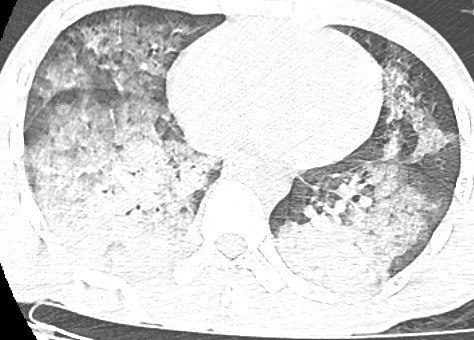

phoi-dong-duoi-nuoc.jpg

Hình ảnh kính mờ (ground-glass opacity) kèm đông đặc phế nang trên phim chụp CLVT của người bệnh Đ. - Ảnh BVCC